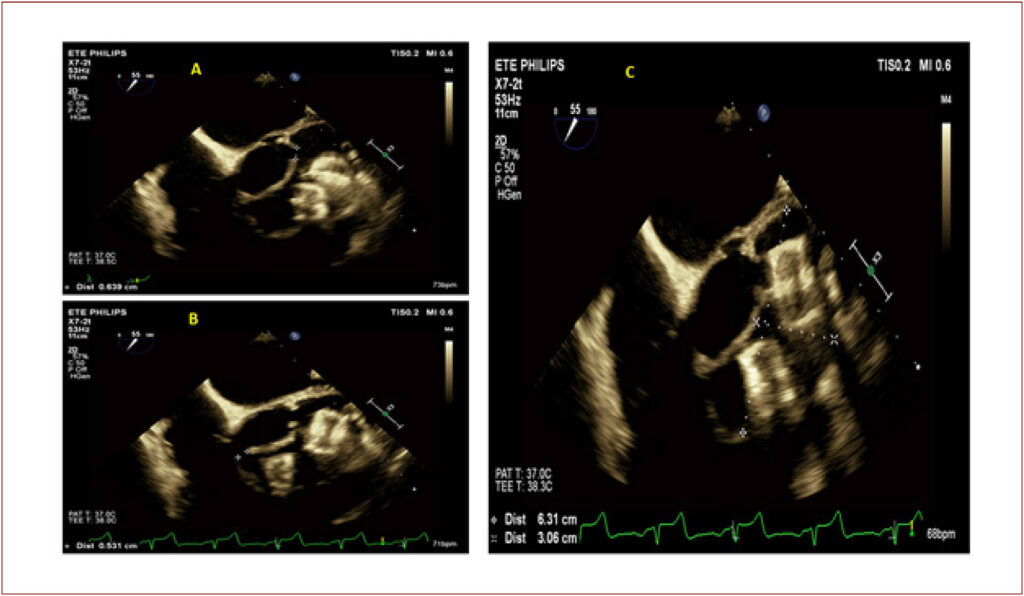

Acidente Vascular Encefálico Isquêmico em Paciente com Pseudoaneurisma na Via de Saída do Ventrículo Esquerdo de Difícil Tratamento

Há relatos de ocorrência de neocavidades cardíacas, frequentemente associadas à pseudoaneurismas decorrentes de lesões traumáticas ou abscessos peripróteticos fistulizados para o ventrículo esquerdo (VE).

Os pseudoaneurismas cardíacos, de forma geral, são associados a complicações de infarto agudo do miocárdio, mas também podem surgir no pós-operatório tardio de cirurgias valvares. Em específico, certas regiões apresentam um potencial favorável para o desenvolvimento de pseudoaneurismas de aorta ascendente. Esses eventos geralmente ocorrem nos locais de canulação e clampeamento aórtico, bem como nas zonas de suturas de enxerto.